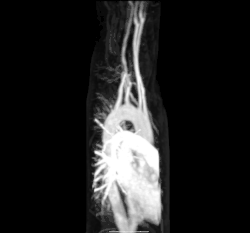

Магнитно-резонансная ангиография аберрантной подключичной артерии.

Многие из этих заболеваний называются «болезнями образа жизни», потому что они развиваются с течением времени и связаны с отношением человека к физическим упражнениям, диетой, курением и другими чертами образа жизни конкретного человека. Предшественником многих из этих заболеваний является атеросклероз, при котором на стенках средних и крупных артерий образуются атероматозные бляшки. В конечном итоге это может привести к закупорке или даже разрыву артерии. Склероз артерий также является фактором риска острых коронарных синдромов, которые представляют собой заболевания, характеризующиеся внезапным дефицитом насыщенной кислородом крови в ткани сердца. Атеросклероз также связан с такими проблемами, как образование аневризм или расщепление («расслоение») артерий[24].

Ещё одно серьёзное сердечно-сосудистое заболевание связано с образованием тромбов. Они могут возникать в венах или артериях. Тромбоз глубоких вен, который чаще всего возникает в ногах, является одной из причин тромбов в венах ног, особенно когда человек находится в неподвижном состоянии в течение длительного времени. Эти сгустки могут эмболизироваться, то есть перемещаться в другое место в организме. Результатом этого может быть лёгочная эмболия, транзиторные ишемические атаки или инсульт[24].